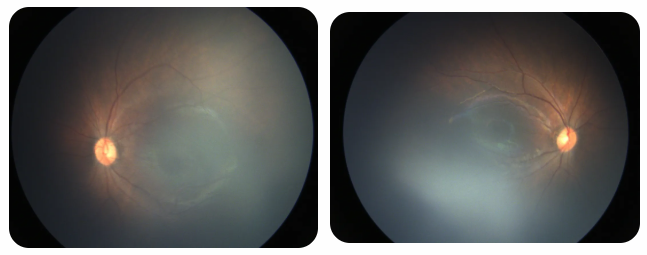

廈門眼科中心黎曉新名醫(yī)工作室曾接診一名31周出生的早產(chǎn)兒,出生體重僅1300克。由于家長(zhǎng)缺乏篩查意識(shí),直到孩子5個(gè)月大時(shí)眼睛仍不會(huì)追光,才前來就診。檢查發(fā)現(xiàn),患兒ROP已進(jìn)展至4B期,因纖維血管增殖牽拉導(dǎo)致視網(wǎng)膜脫離,錯(cuò)過了最佳治療窗口。盡管黎曉新教授團(tuán)隊(duì)成功實(shí)施了玻璃體切割手術(shù),孩子的視力仍存在不可逆損傷。此后,孩子開啟了長(zhǎng)期隨診復(fù)查、治療的“護(hù)眼征程”,目前其右眼矯正視力為0.6,左眼為0.8。

近期術(shù)前檢查:

早產(chǎn)兒視網(wǎng)膜病變

術(shù)后復(fù)查:

相比之下,另一位早產(chǎn)寶寶在出生5周后,生命體征穩(wěn)定之時(shí),便在產(chǎn)科醫(yī)生的建議下轉(zhuǎn)診至廈門眼科中心。經(jīng)篩查確診為Ⅲ期ROP,黎曉新教授團(tuán)隊(duì)及時(shí)為其進(jìn)行了激光治療。半年后復(fù)查顯示,寶寶的視網(wǎng)膜血管發(fā)育正常,視力發(fā)育與足月兒童無(wú)異。